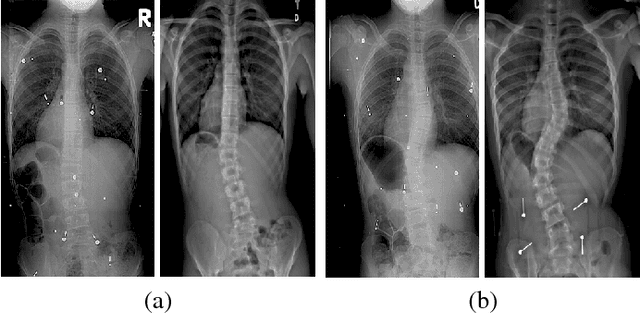

We introduce a novel approach for predicting the progression of adolescent idiopathic scoliosis from 3D spine models reconstructed from biplanar X-ray images. Recent progress in machine learning have allowed to improve classification and prognosis rates, but lack a probabilistic framework to measure uncertainty in the data. We propose a discriminative probabilistic manifold embedding where locally linear mappings transform data points from high-dimensional space to corresponding low-dimensional coordinates. A discriminant adjacency matrix is constructed to maximize the separation between progressive and non-progressive groups of patients diagnosed with scoliosis, while minimizing the distance in latent variables belonging to the same class. To predict the evolution of deformation, a baseline reconstruction is projected onto the manifold, from which a spatiotemporal regression model is built from parallel transport curves inferred from neighboring exemplars. Rate of progression is modulated from the spine flexibility and curve magnitude of the 3D spine deformation. The method was tested on 745 reconstructions from 133 subjects using longitudinal 3D reconstructions of the spine, with results demonstrating the discriminatory framework can identify between progressive and non-progressive of scoliotic patients with a classification rate of 81% and prediction differences of 2.1$^{o}$ in main curve angulation, outperforming other manifold learning methods. Our method achieved a higher prediction accuracy and improved the modeling of spatiotemporal morphological changes in highly deformed spines compared to other learning methods.